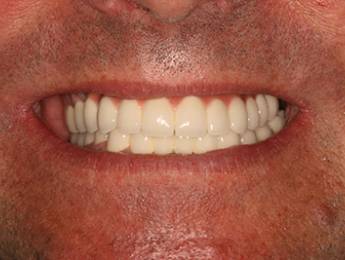

1. eset

A páciens fogágybetegség miatt érkezett hozzánk. A felső fogak menthetetlen állapotban voltak. All on 6 megoldásként a felső fogak eltávolításakor 6 implantátum került beültetésre és a páciens azonnal egy fix ideiglenes hidat kapott. 4 hónapos gyógyulási idő után készült el a felső fémkerámia leplezésű körhíd.